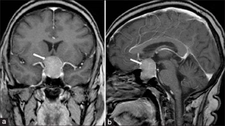

Tanı YöntemleriAkciğer tümörü tanısı, hastanın belirtileri ve fiziksel muayenesi ile başlayarak çeşitli testler ile devam eder. Tanı yöntemleri arasında: